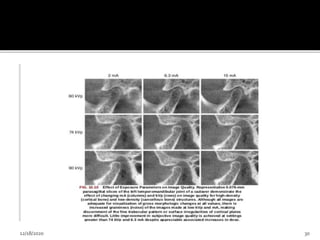

3. Scan time and number of projection

Adjusting the detector frame rate

Increase the number of basis image projections

Reconstructed image with fewer artifacts and better

image quality

2.Spatial resolution • Abilityof an image to reveal fine detail. • Determined by i. Pixel size ii. Beam projection geometry iii. Patient scatter iv. Focal spot size v. Number of basis image vi. Reconstruction algorithm 12/18/2020 31